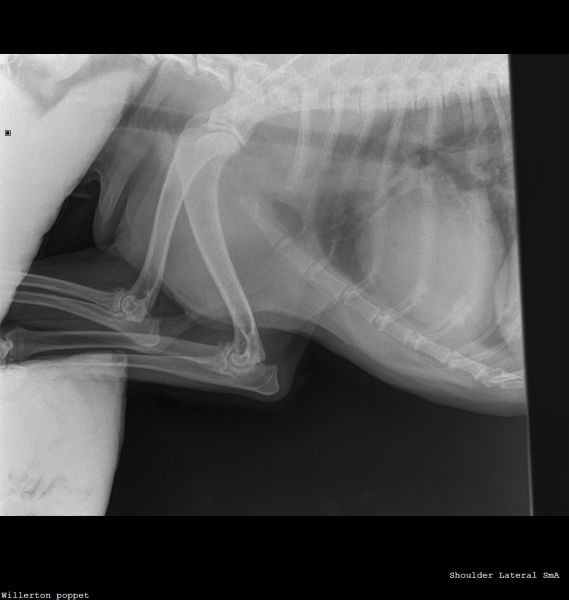

Hi vets, Wondered if anyone could give a second opinion on these X-rays? 12 year old dog. Left forelimb lameness improved with antibiotics then got worse again. Gradually worsening over the past 3 months. Pain on palpation around the left wrist joint and has been treated for an infected claw on the left paw 8 weeks ago (the starting incident for vet treatment). Muscle loss around left shoulder and now winging from the elbow. My first practitioner vets have sent it off for an orthopaedic consult but in the meantime it would be nice to settle my brain that nothing terrible is happening with my dog 🤞🏻 Thank you 🙏🏻Willerton_poppet_CARPUS-Carpus Dorso-palmaWillerton_poppet_SHOULDER-Shoulder Lateral(1)Willerton_poppet_SHOULDER-Shoulder Lateral

Hello and thank you for this interesting question.  With my harsh scientific hat on rather than my people-hat, I can point out that nobody can tell you even from a very comprehensive series of x-rays that nothing terrible is happening with your dog; however, investigation of any areas of concern is always a good way forward. We do not read radiographs as part of this series; I have no additional qualifications in reading radiographs so this is best done by the vet who has the full context available to them and if they are unsure, then an expert.  Sometimes if experts are unsure, they will offer further tests or a biopsy.  My job is to help you to get the best out of your vet and I, perhaps like your vet, am a little concerned about the way some of these joints present on the radiograph.  It therefore seems a good idea to maximise the effectiveness of the radiographs already taken, to ask for the comment of an expert.  This seems a reasonable and appropriate next step. Lameness is usually a reflection of pain; the fact that an animal is lame tends to imply that it hurts to put the leg down properly.  The changes to the nail may have been part of a cause of this (for example, fungal infection affecting bone causing pain,  not the only possibility) or part of a consequence of this (ie lameness / altered weight-bearing causing damage to the nail).     It  may be worth asking whether your pet can have pain relief in the meantime, in order to make them more comfortable.  Wishing you the best of luck with this case going forward; please would you let us know how your chihuahua gets on?